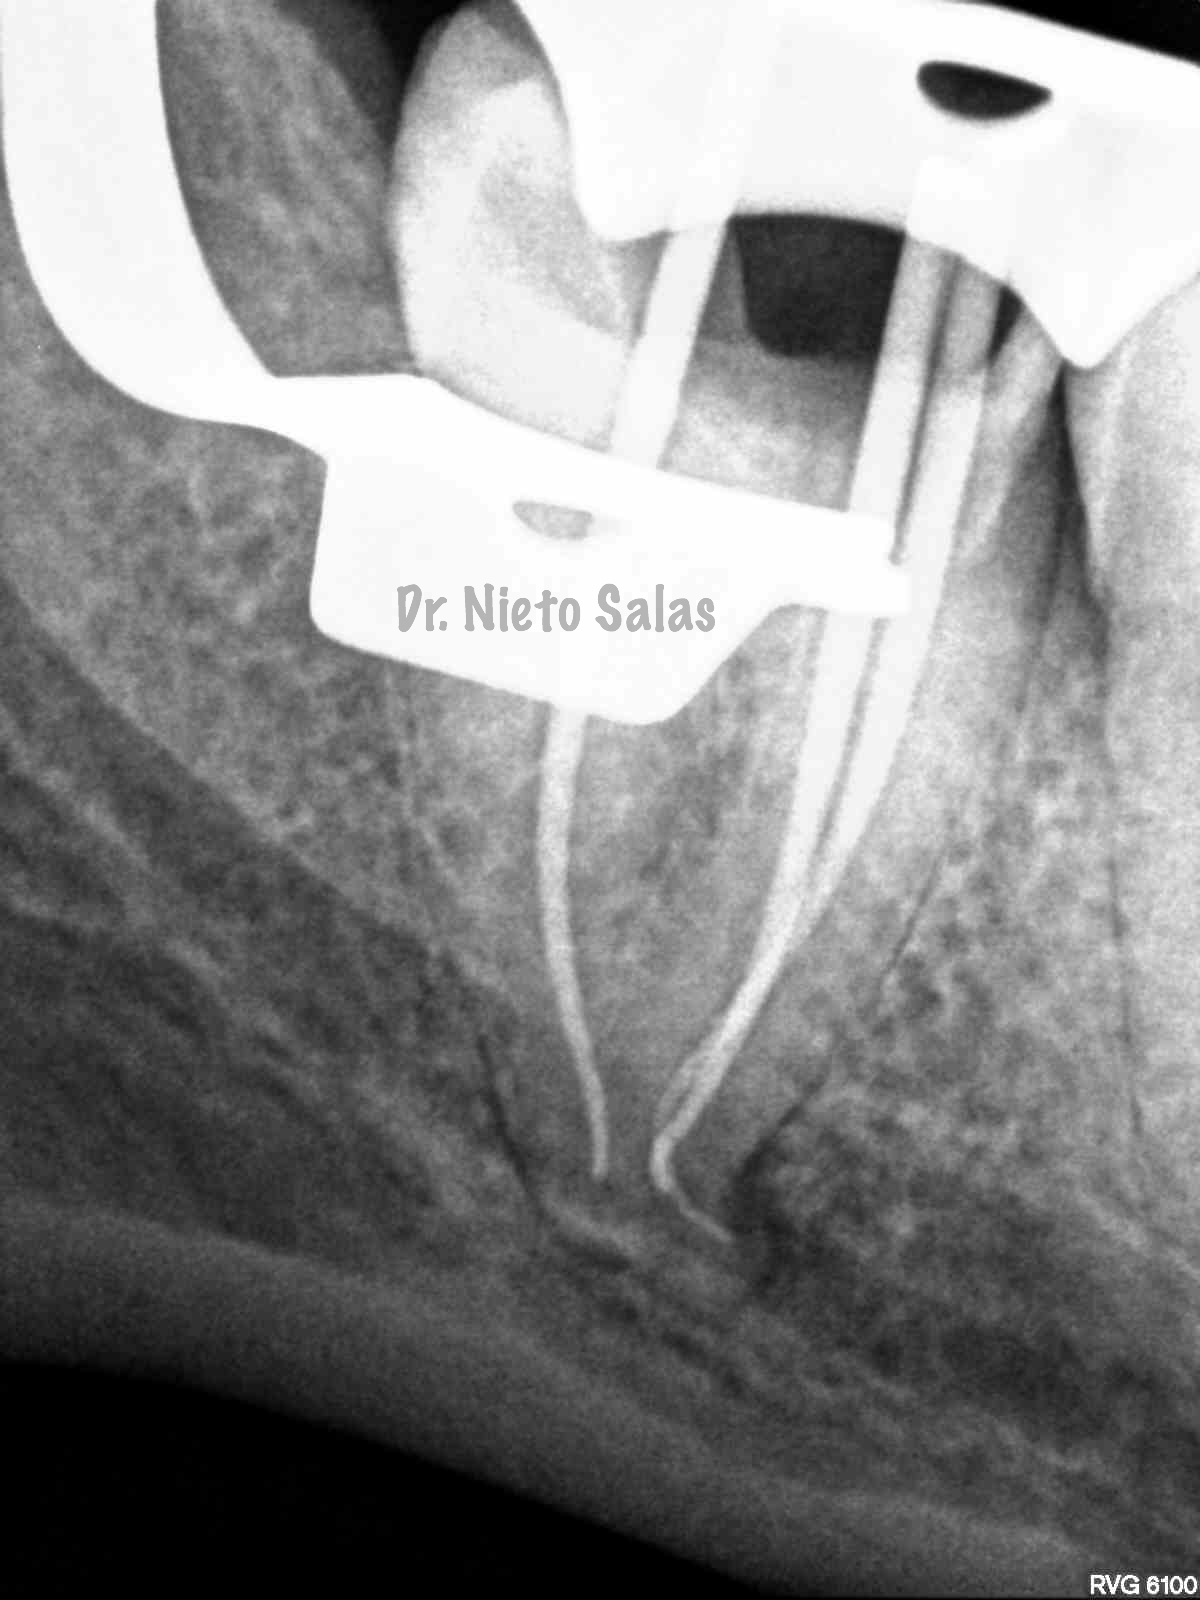

Bueno , ante esta piezas, que presentan una periodontitis apical crónica en la 4.7 y una pulpitis irreversible en la 3.7 nos disponemos a realizar le tratamiento de conductos.

Intentamos mantener la permeabilidad y la forma de  los conductos. Instrumentamos con Pathfile y Mtwo hasta un 25-6%.

(ORTO)                                                               (DISTO)

(MESIO)